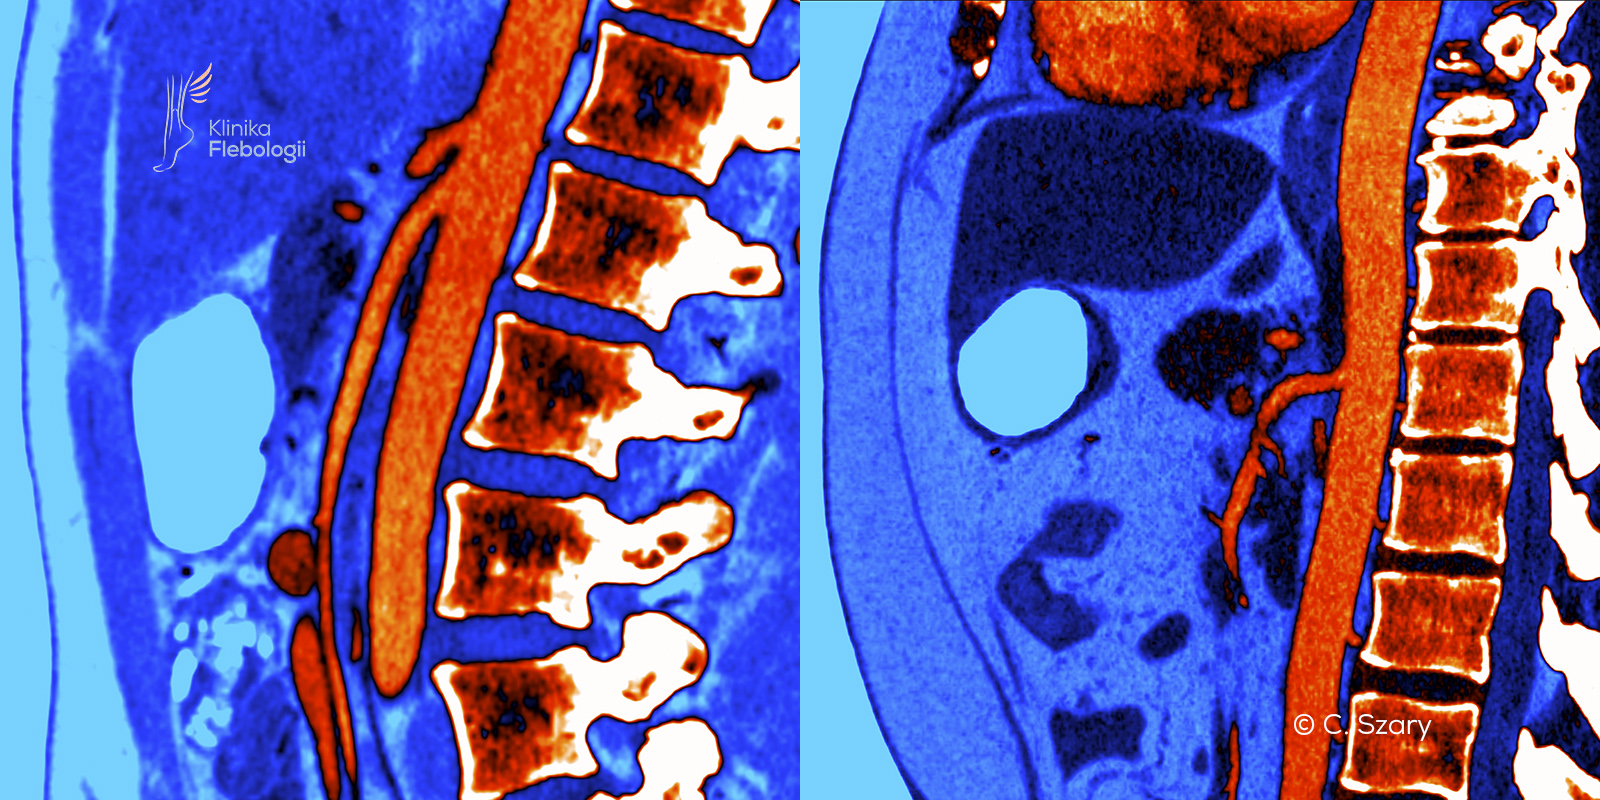

Zespół dziadka do orzechów związany jest ze zjawiskiem zaburzonego odpływu krwi żylnej z obszaru spływu lewej żyły nerkowej. Do ucisku lewej żyły nerkowej dochodzi najczęściej w miejscu jej krzyżowania na poziomie tętnicy krezkowej górnej (wariant przedni) lub w przypadku jej zaortalnego położenia (wariant tylny).

Zjawisko dziadka do orzechów należy do najczęstszych pierwotnych wariantów uciskowych na spływy żylne w organizmie człowieka. Najczęściej obserwujemy je na poziomie skrzyżowania lewej żyły nerkowej i tętnicy krezkowej górnej tuż pod jej odejściem od aorty brzusznej.

Zespół dziadka do orzechów typowo powstaje w sytuacji, gdy tętnica krezkowa górna pod bardzo małym kątem odchodzi od aorty brzusznej, tylko nieznacznie się odchylając i wyginając. Sytuację pogłębia zazwyczaj uwydatniona lordoza lędźwiowa.